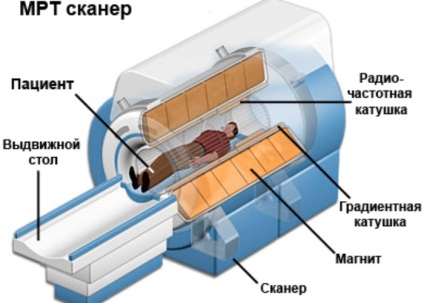

A működési elve az MRI

Ha a kezelést a gerinc MRI a lumbosacral beteg kerül egy mozgatható asztal diagnosztikai rögzített speciális felépítményekkel minimalizálása mozgását. A táblázat kerül egy kapszulába gép, amely diagnosztikai beállítást. A mágnes található érintett terület - az ágyéki és a gerinc.

Egy felmérésben lágy szöveti struktúráit ágyéki és részei a mátrixot járulékosan alkalmazott felületi tekercs.